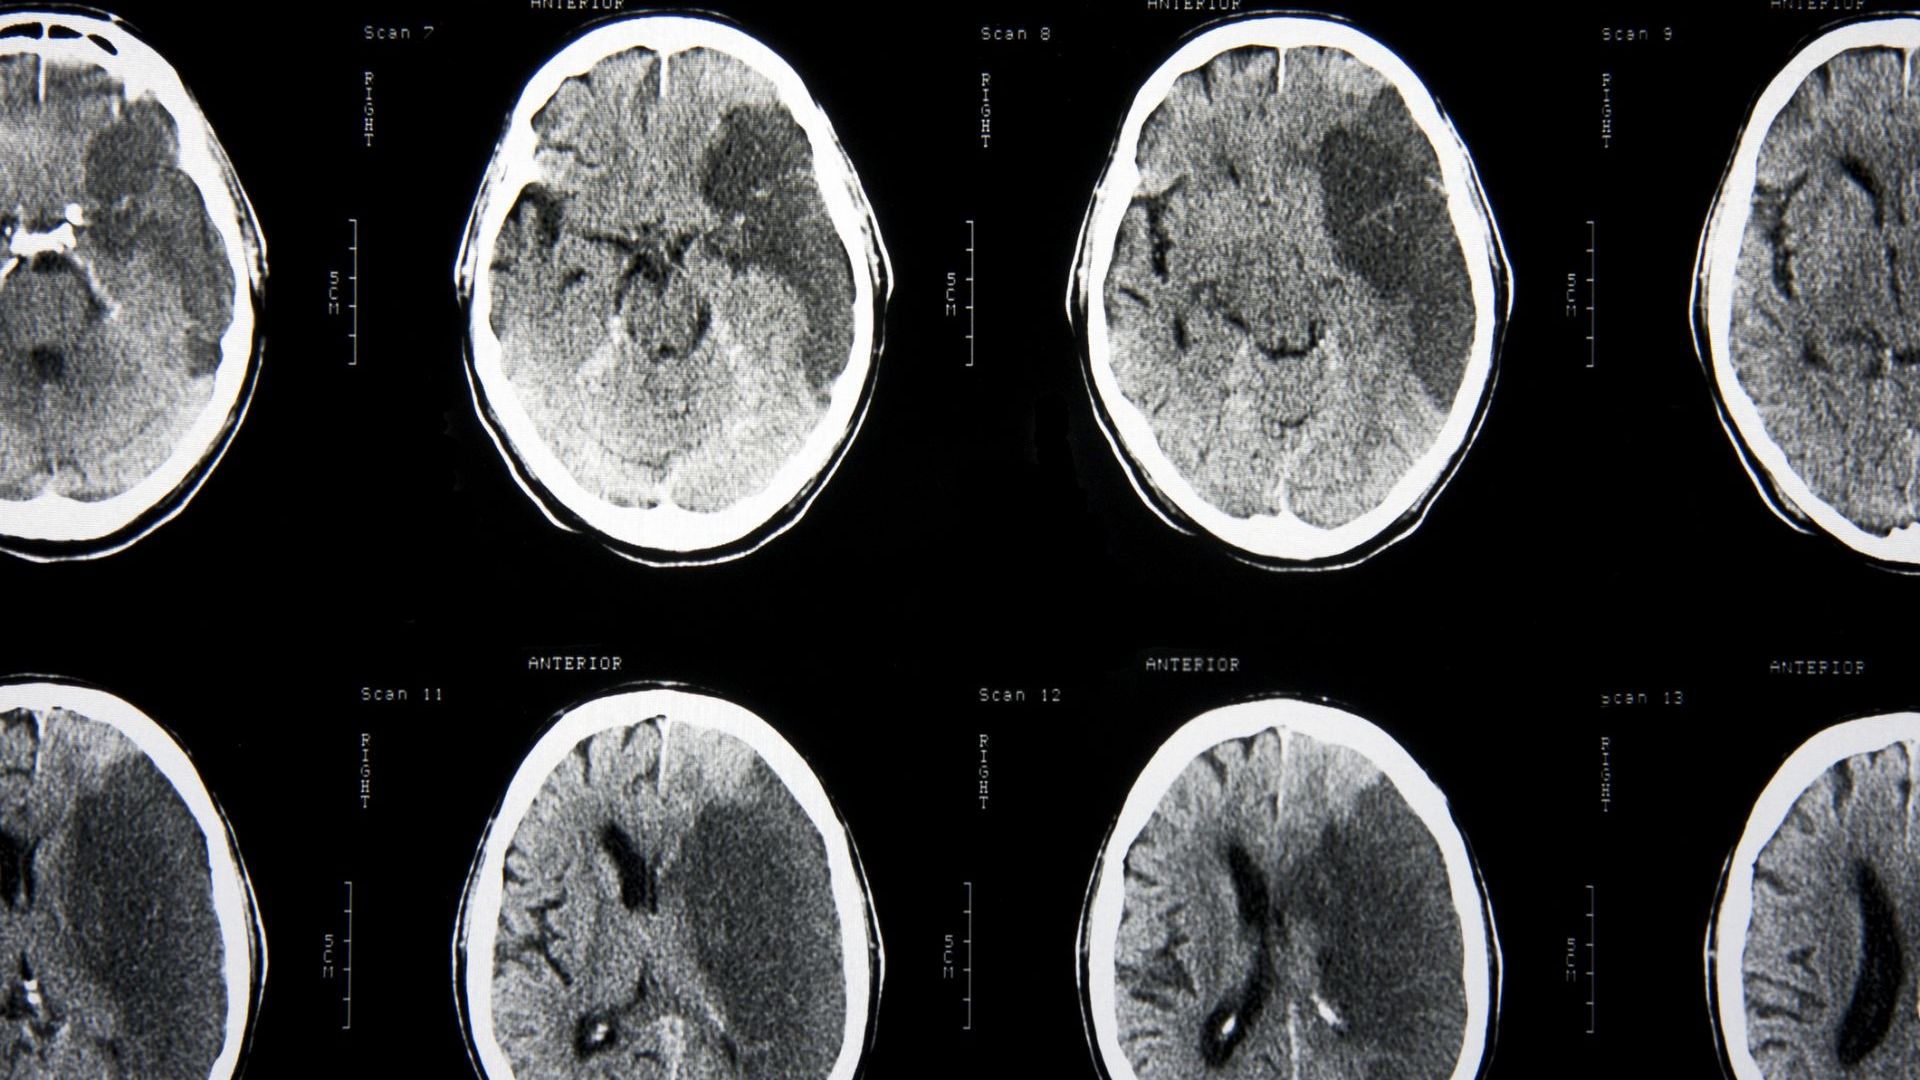

Намира и разтваря кръвни съсиреци в мозъкаПредставете си че можем

Лекува Инсулт - Новини